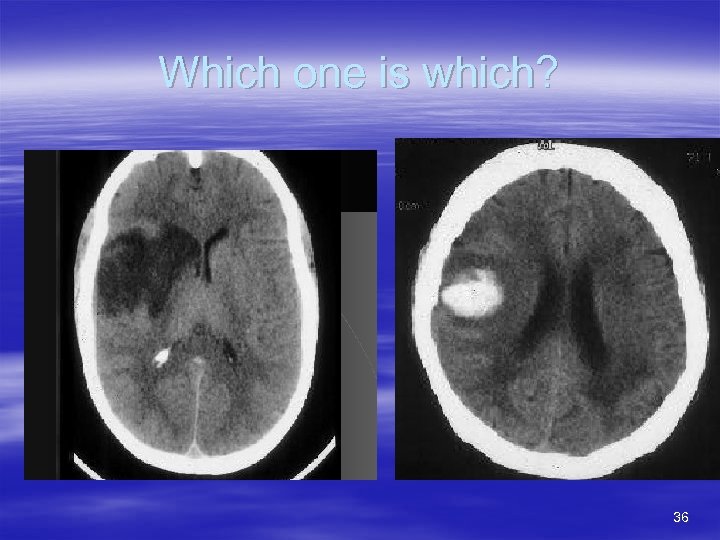

Treatment considerations (cont’d) § § § Time from onset (Remember 3 hours) Stroke severity Stroke subtype – Data driven here too § CT findings – Assymetry = Bad – Density image – Tissue/fluid ratio § § Charcoal=Normal Dark = Higher density (more tissue than fluid) – Ischemia § Light = Lower density (More fluid than tissue) – Hemorrhage – Tumor 35

Which one is which? 36